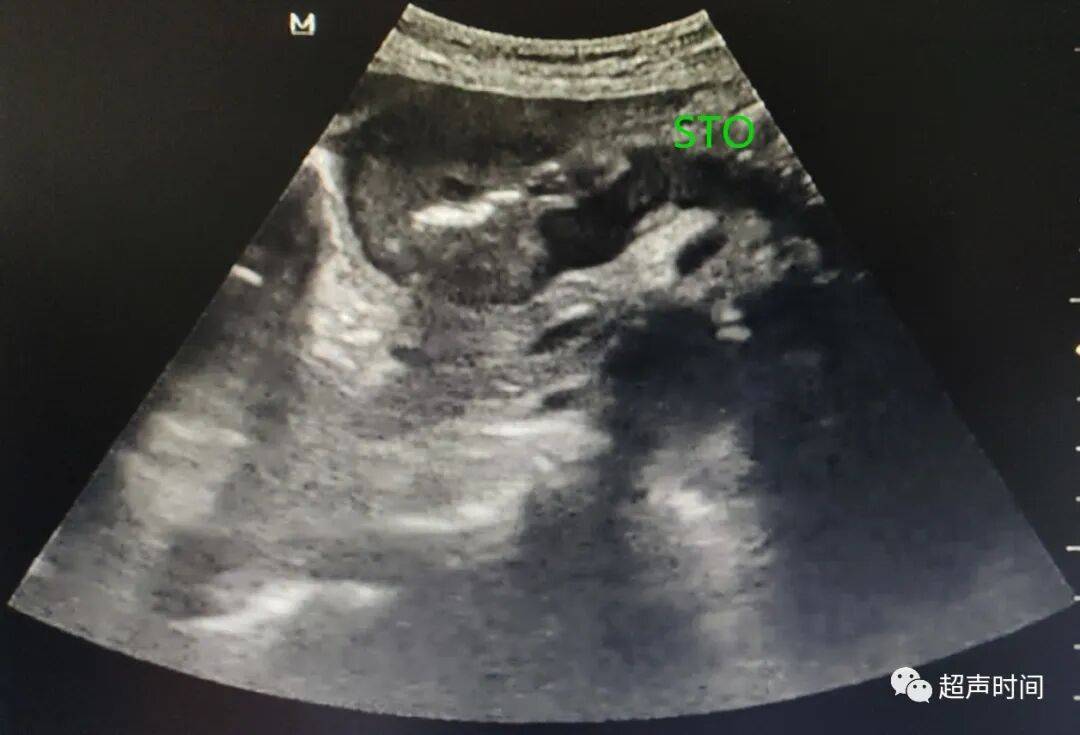

胃窦壁不规则增厚,回声减低, CDFI :其内可见高阻血流。胃窦壁僵直,探头按压长时间不蠕动。余胃壁蠕动良好。

图 1

图 3 胃窦纵切:胃窦壁不规则增厚,回声减低,僵直不蠕动